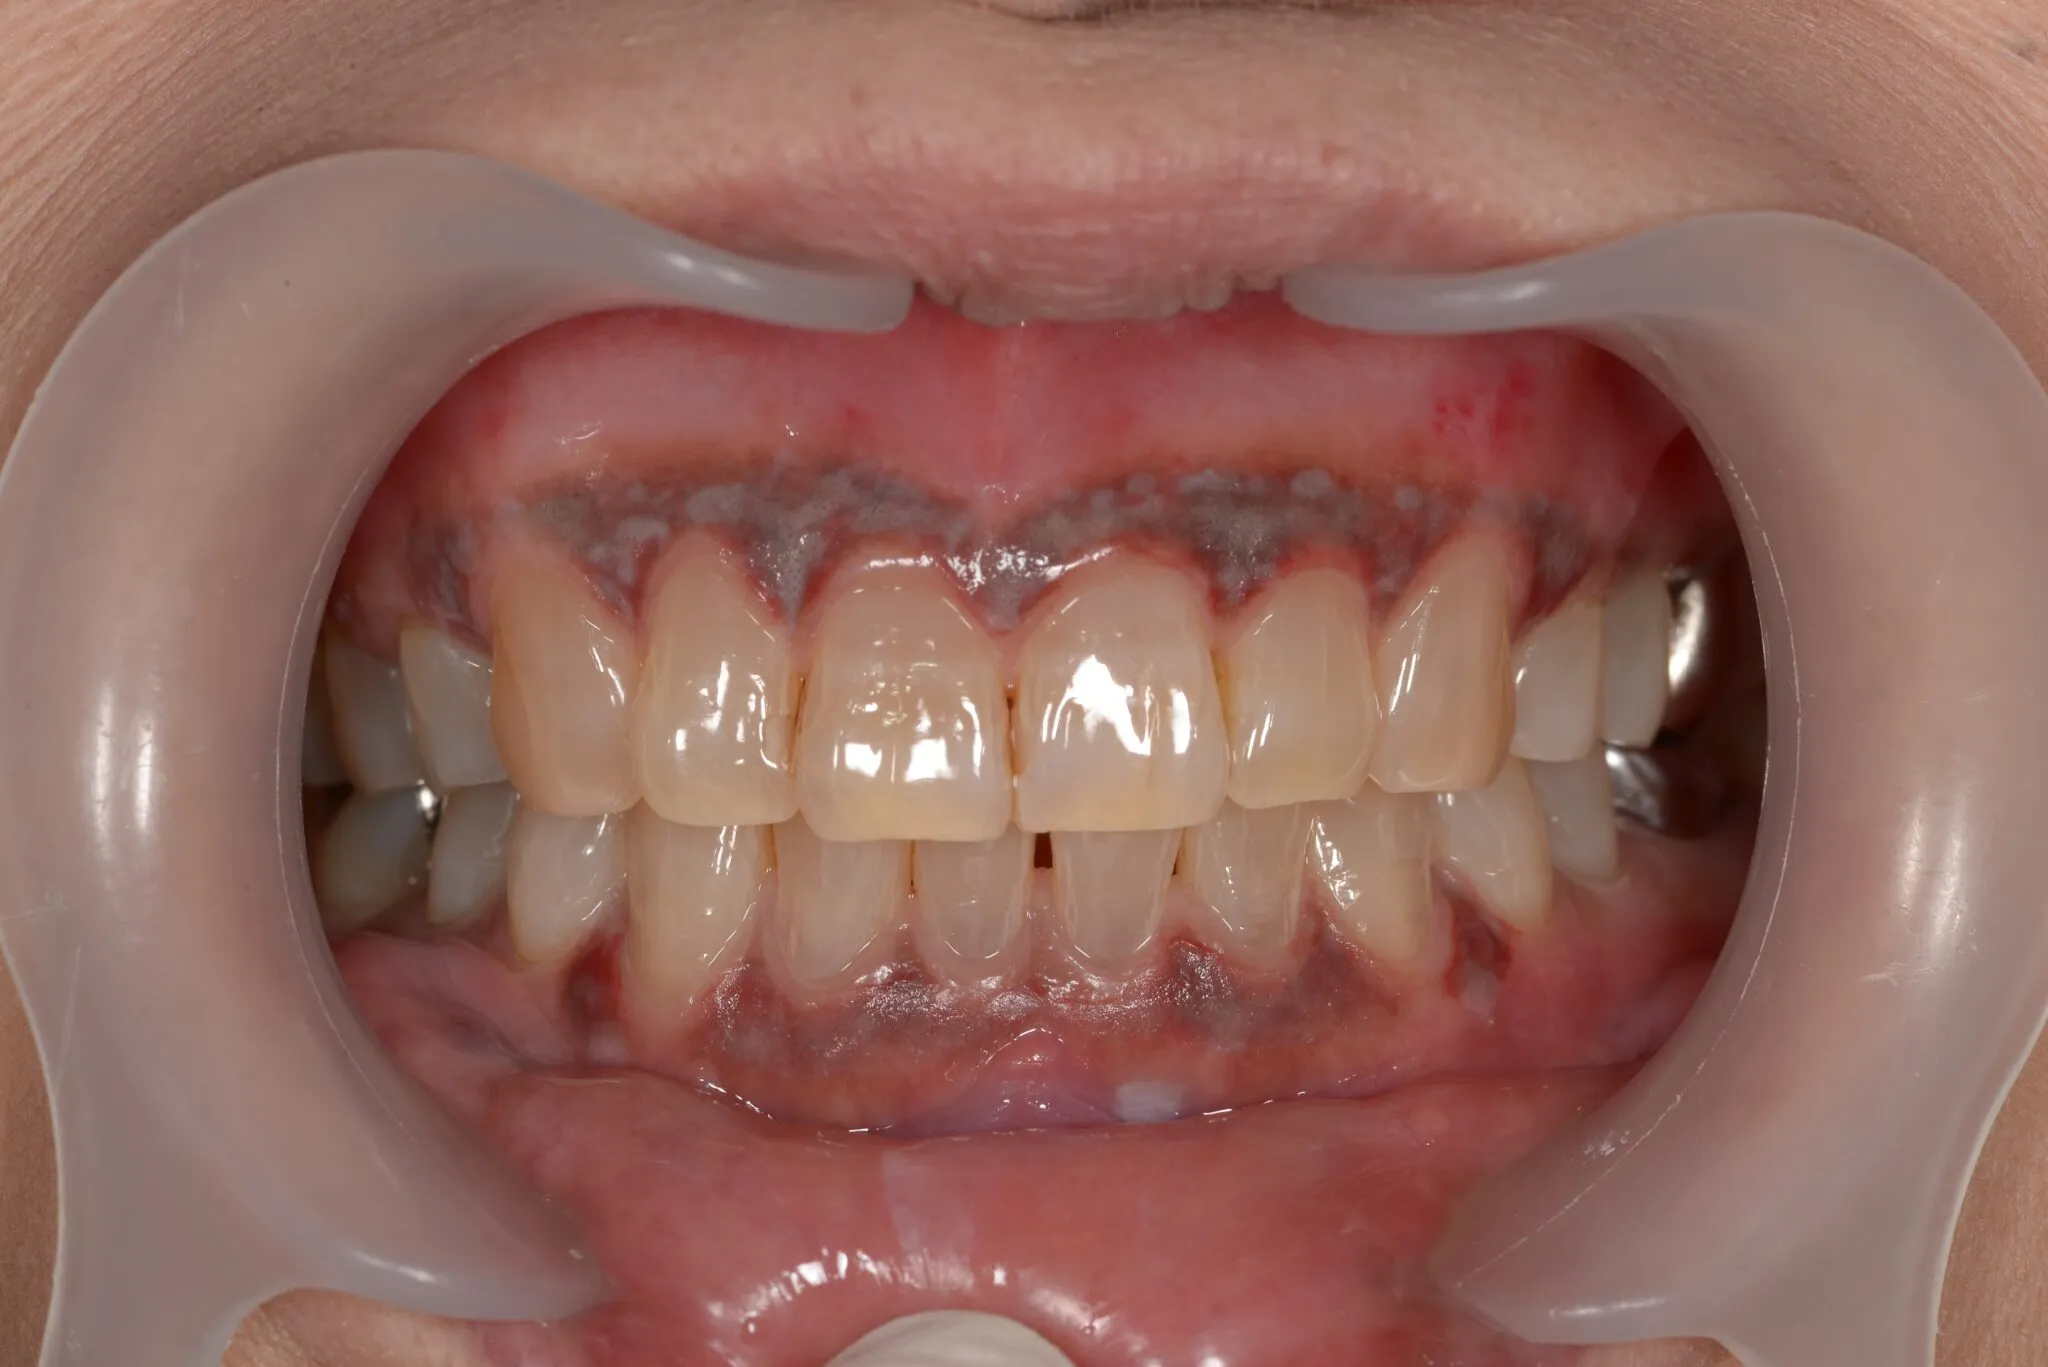

ガムブリーチ

歯の色を白くするのが通常のホワイトニングですが、歯肉が黒ずんでいるのを通常に戻すのがガムブリーチです。

歯肉はメラニン色素が付着すると黒ずんできますので、その歯肉の部分をメラニン色素除去剤で中和します。

Before

After

治療内容 | 歯肉の着色を薬液を用いて表面を一層除去し新鮮面を出す |

---|---|

治療期間 | 30分 |

治療回数 | 1回 |

リスク | 処置後数日は疼痛がある場合がある |

費用(税込) | ¥27,500 |

歯肉はメラニン色素が付着すると黒ずんくるため、その歯肉の部分をメラニン色素除去剤で中和するという処置を行います。

メリット

術後の回復が早い

ダウンタイムがない

デメリット

アレルギーがある場合には適応できない

歯肉退縮のリスクがある

治療期間 | 1ヶ月程 術後観察が半年〜1年必要 |

治療回数 | 約4回 |

費用(税込) | ¥110,000~¥165,000/本 |